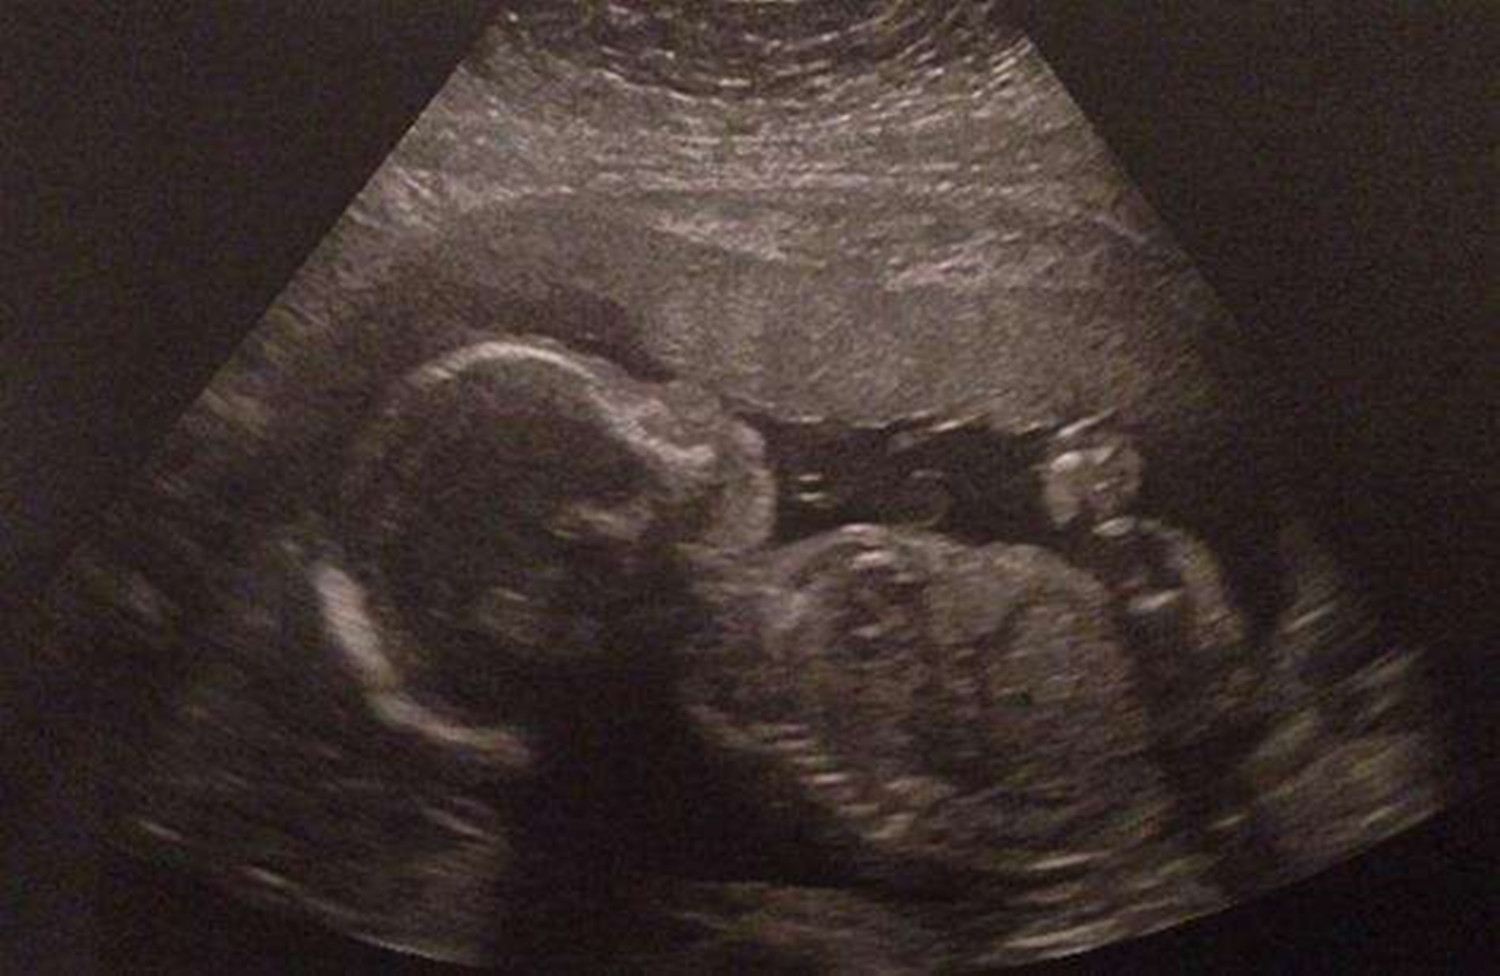

胎动,是指胎儿在子宫腔里的活动冲击到子宫壁的动作。胎儿在子宫内伸手、踢腿、冲击子宫壁,这就是胎动。

胎动是现代医疗技术中,辅助观察胎儿在子宫内是否健康的一个较为有效的办法。

一般孕妈满四个月后,开始感到胎儿的明显活动,医生或孕妇可以根据胎动的次数多少、快慢强弱等来检测胎儿的安危。